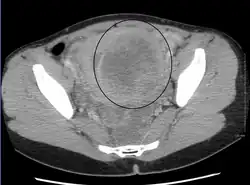

A relatively large submucosal leiomyoma; it fills out the major part of the endometrial cavity. -

A subserosal uterine fibroid with a diameter of 5 centimeters -